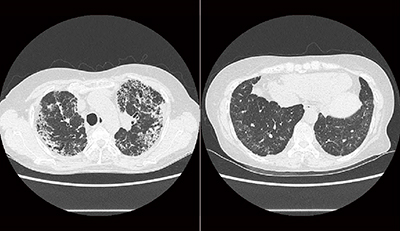

胸部単純X線写真では,上肺野優位の網状影,浸潤影が認められる。単純CT画像(図4)では,上肺野に強い網状影とコンソリデーションが認められた。胸部X線動態画像(図5)では全体的に動きが悪く,横隔膜の動きも不自然で,側面像では肺の下葉が呼吸を支えているという印象である。変位のベクトル表示画像(図6)でも肺野全体の動きが悪い印象であった。

図6 症例2:変位のベクトル表示画像